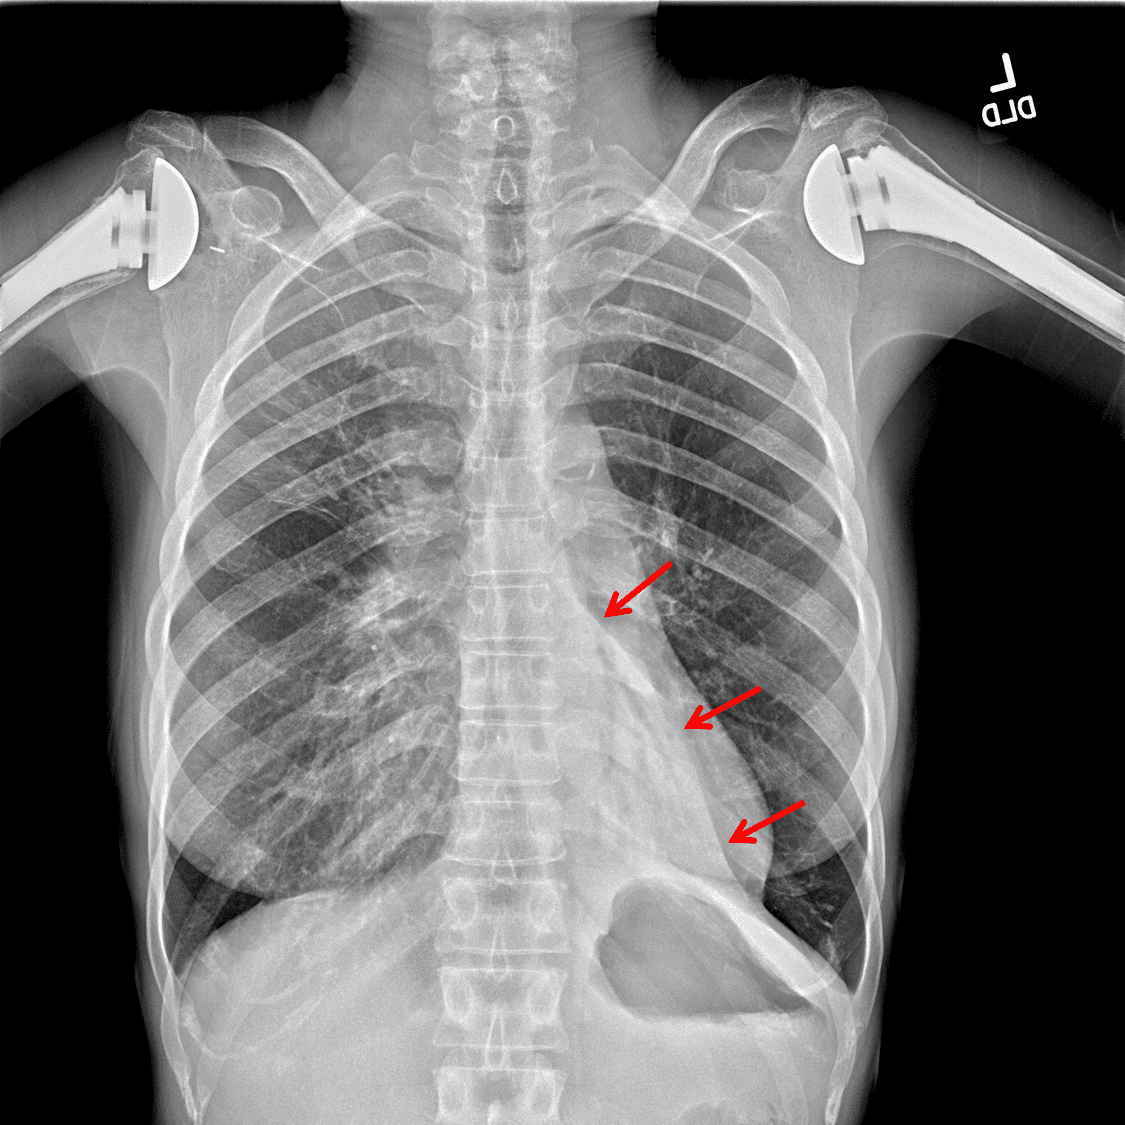

Sample ReportOpacification and volume loss in the left lower lobe consistent with lobar collapse. Intermixed bronchiectasis may relate to chronic infection or mucous plugging. Consider obtaining a chest CT to exclude a central obstructing mass.